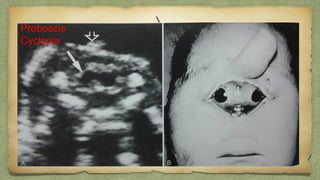

Proboscis

Cyclopia

Hypertelorism